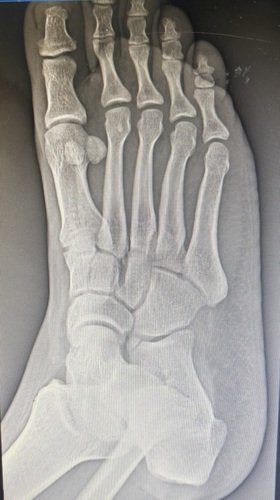

Me chamo Fernando, hoje venho aqui pedir a sua ajuda em um momento muito difícil da minha vida. Recentemente, sofri um acidente de moto e fraturei o calcanhar e outros 3 lugares do meu pé, o que me impossibilita de andar e, consequentemente, de trabalhar. Além da dor física e das limitações, estou enfrentando um grande desafio financeiro, pois minha principal fonte de transporte e renda – minha moto – ficou muito danificada e o conserto ficou em R$ 3.600,00, foi preciso fazer um reparo no chassi, oque fez encarecer ainda mais o valor do serviço, e infelizmente não consigo arcar com esse custo agora. Autorizei o serviço numa oficina da minha confiança e pedi pra eles irem fazendo o serviço aos poucos para que eu pudesse me recuperar do me organizar financeiramente para conseguir retirar a moto da oficina.